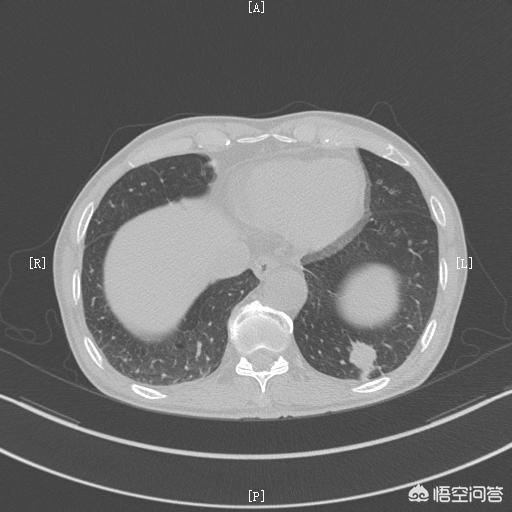

肺がん。

なぜ肺がんになると胸のつかえや息切れが起こるのでしょうか?肺がんの病巣が比較的大きい場合、気管支の一部が閉塞し、肺機能に影響を及ぼし、その結果、以下のような症状が現れるからです。胸のつかえ、息切れ肺がんの症状しかし一般的に、肺がんに胸のつかえや息切れが見られる場合は、肺がんが進行していることを意味します。進行した肺がんだ。なぜなら、一般的に肺がんの初期症状は目立たない。

中程度から進行した肺がんの場合、胸部圧迫感や息切れに加えて、胸が苦しくなることもある。鈍痛、漠然とした痛みなど中枢性肺がんの場合、次のようなこともある。咯血などの症状がある。

肺がんの診断で最も重要なのは画像診断で、胸部X線検査で病変が大きい肺がんは発見できるが、小さい肺がんの場合は、肺がん検診を受ける必要がある。胸部CTスキャンを診断する。胸部CTスキャンも肺がんのスクリーニングと診断に最適な方法です。これに加えて、多くの場合、以下のことが可能です。ファイバーオプティック気管支鏡検査またはCTガイド下穿刺病変から組織を採取し、病理学的生検を行うなどの検査が、ゴールドスタンダード診断につながる。

肺がんと診断されたら、外科的治療が可能な患者には、以下のことが重要である。積極的な外科的除去肺がんを治す唯一の方法であり、外科的切除による治療が不可能な患者には、次のような選択肢がある。化学療法、免疫療法、標的療法など。質を改善し、生存期間を延長するためのその他の治療法。